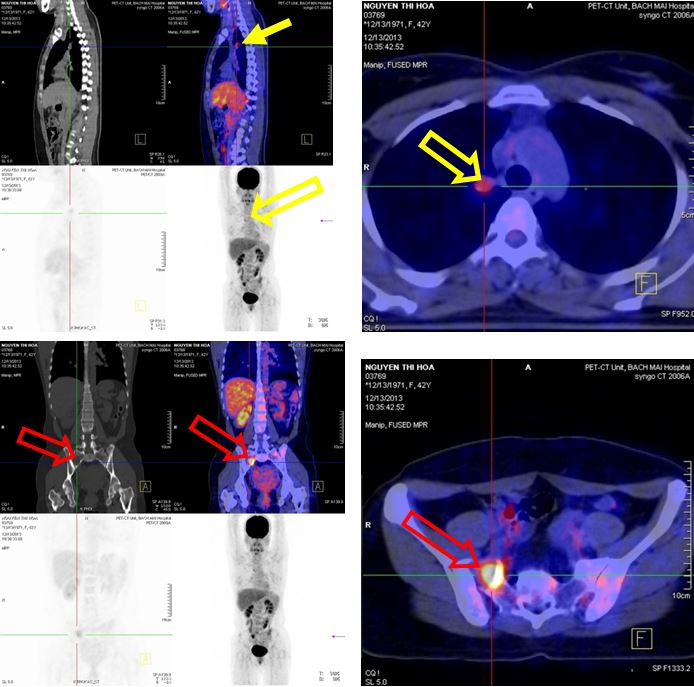

1. Chụp PET/CT sau điều trị 1 tháng:

Nhu mô hai phổi không thấy tổ chức hấp thu F-18 FDG bất thường, không thấy tràn dịch màng phổi.

- Hạch rốn phổi phải đường kính 0,9cm, tăng hấp thu F-18 FDG, max SUV=2,8.

- Xương chậu phải tăng hấp thu F-18 FDG, max SUV=6,17

Hình khuyết xương thân D10 không tăng hấp thu F-18 FDG

Hình 9: Hình ảnh PET/CT sau điều trị 1 tháng cho thấy hạch trung thất kích thước 0,9 cm tăng hấp thu F18-FDG với max SUV=2,8 (đầu mũi tên vàng), xương chậu phải tăng hấp thu F18-FDG với max SUV=6,17 (đầu mũi tên đỏ)